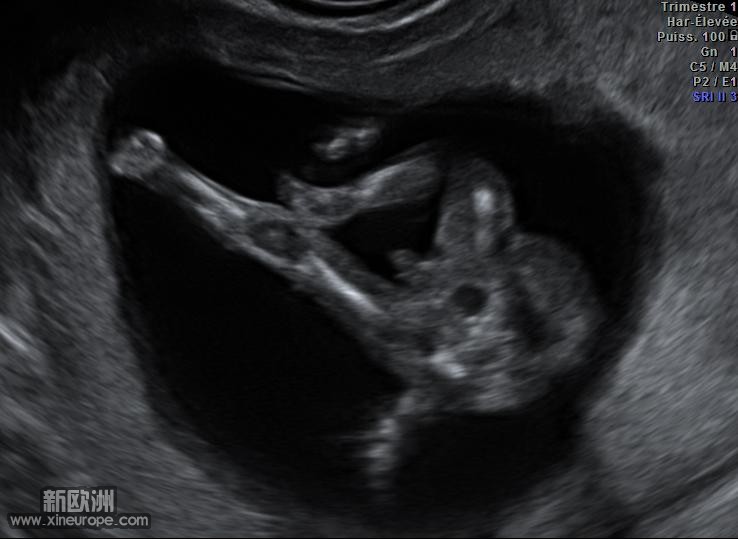

12周bc图小玩,就是娱乐下无聊帖

图1明明看到小JJ了嘛,SESE,你不用太疑心了,我看10之8,9你家二宝是姑娘。医生没个8成把握不会说的。

不过,大脑袋到是看的清清楚楚

嘻嘻,照片来啦。

13sa.JPG

想想真是神奇啊,他那时候才7,5厘米的身长,居然看的这么清楚啦。

刚看了下我家妞十个多周的BC图

呵呵,那个角度跟sese的二宝差不多

好神奇啊,说不定蛮准的

sese的二宝应该是个女孩啦